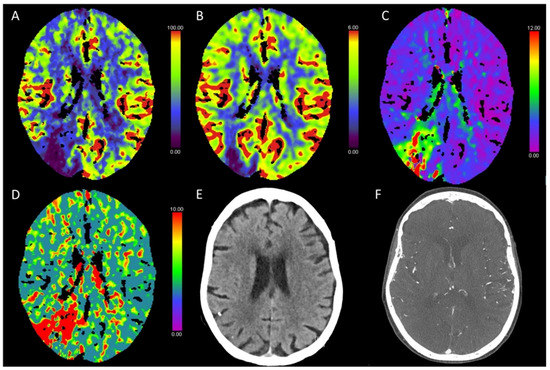

3.3. Global Hypoxic-Ischemic Injury/Brain Death

3.5. Hypotensive Cerebral Infarction (HCI) with Watershed Infarcts/Border Zones